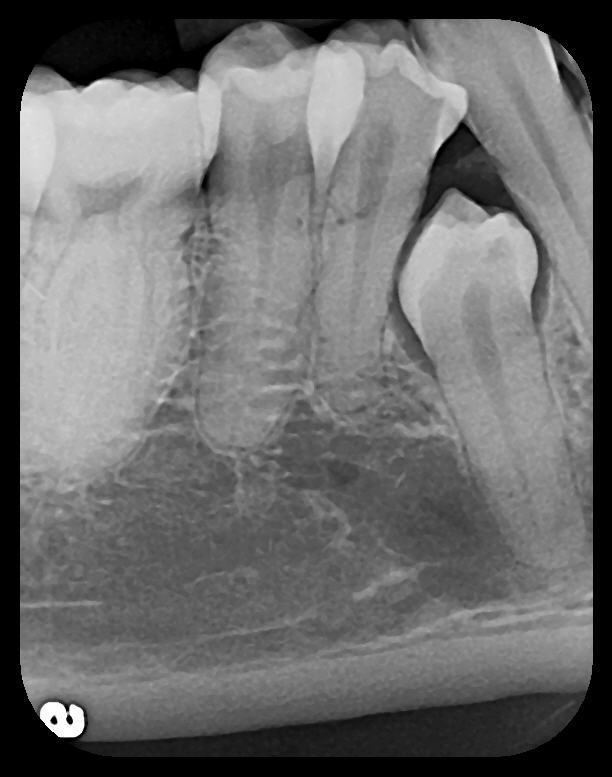

Fig 2. Left: PSP vertical PA radiograph of

maxillary bicuspid area demonstrating full root structure, several millimeters of bony anatomy beyond apices and maxillary sinus. Tooth No. 4 may be

traumatized as periodontal ligament is widened. Right: PSP horizontal PA radiograph of maxillary bicuspid area. Tooth No. 12 shows widened apical

periodontal ligament presumably caused by deep restorative filling. Some loss of supporting bone is evident interproximally, especially pronounced

between tooth Nos. 14 and 15.

Figure 2